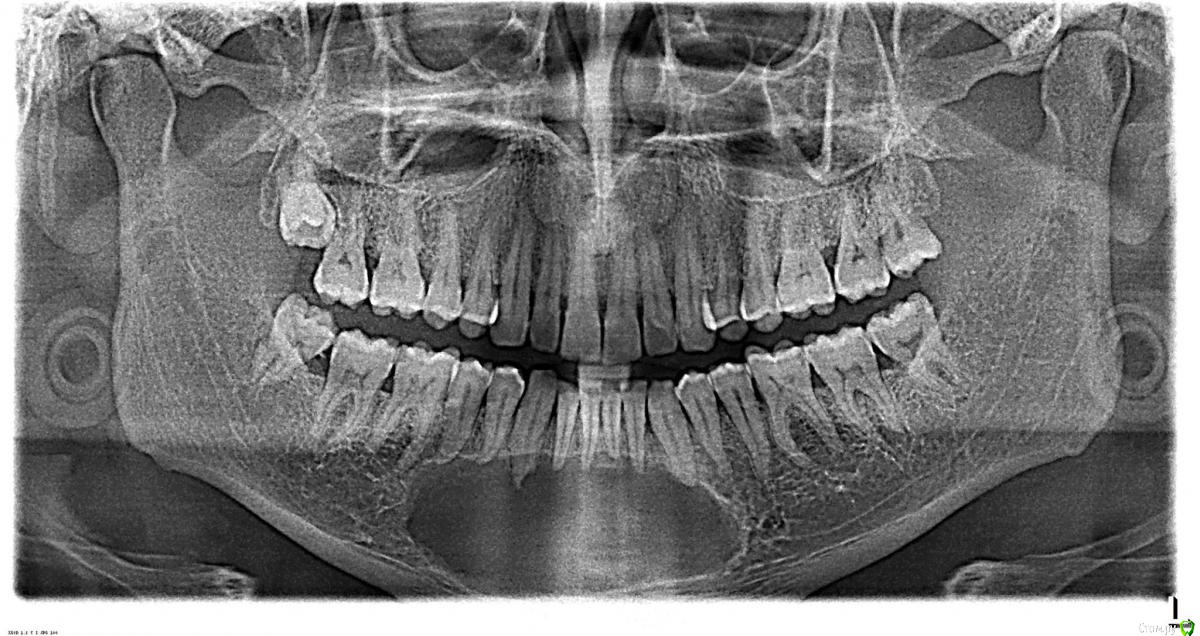

dentikl Опубликовано 22 декабря, 2016 Автор Поделиться Опубликовано 22 декабря, 2016 Потому что дефект 3-х стеночный и не выходит за границы контура челюсти,об'ем конечно кости уменьшаетсявот этот случай требует мембраны и индуктора?Ретроградно пломбировать даже если пройду на ревизии? Ссылка на комментарий

dentikl Опубликовано 22 декабря, 2016 Автор Поделиться Опубликовано 22 декабря, 2016 Зачем тогда вообще резекция!!!?там я фотки повесил.с Вашей точки зрения индуктор и мембрана нужны(Вы бы использовали в этом конкретном случае?) Ссылка на комментарий

Доктор Добрых Дел Опубликовано 22 декабря, 2016 Поделиться Опубликовано 22 декабря, 2016 В области 11 случайно не трещина корня? Медиально очаг деструкции как-то намекает на это 1 Ссылка на комментарий

Тимур86 Опубликовано 22 декабря, 2016 Поделиться Опубликовано 22 декабря, 2016 киста сбоку говорит о том что в корне скорее всего трещина Ссылка на комментарий

Bier Опубликовано 22 декабря, 2016 Поделиться Опубликовано 22 декабря, 2016 не трещина там, а латераль скорее всего. Так высоко корень только от удара может сломаться. dentikl методика РВК применяется только при невозможности или безуспешности ортоградного лечения. Т.е. в вашем случае оперировать не нужно, нужно ждать излечения. Если же вы проводите РВК - единственным смыслом этой операции является установка апикальной пломбы, желательно не короче 3-4мм вглубь канала. Прорут, Триоксидент, IRM, или биокерамика - подходят для этих целей. 4 Ссылка на комментарий

dentikl Опубликовано 22 декабря, 2016 Автор Поделиться Опубликовано 22 декабря, 2016 киста сбоку говорит о том что в корне скорее всего трещинаСори.Я дал неудачный вид Ссылка на комментарий

dentikl Опубликовано 22 декабря, 2016 Автор Поделиться Опубликовано 22 декабря, 2016 не трещина там, а латераль скорее всего. Так высоко корень только от удара может сломаться. dentiklметодика РВК применяется только при невозможности или безуспешности ортоградного лечения. Т.е. в вашем случае оперировать не нужно, нужно ждать излечения. Если же вы проводите РВК - единственным смыслом этой операции является установка апикальной пломбы, желательно не короче 3-4мм вглубь канала. Прорут, Триоксидент, IRM, или биокерамика - подходят для этих целей.корни и коронковые настолько выработаны по толщине предыдущими реставрациями,что я не могу вести их терапевтически до победного конца.Ревизия-вкладки-временная реставрация-хирургия.Резекции здесь будут только в случае,если верхушки помешают работе.Теоретически я понимаю-мембрана не нужна.Но столкнулся с заметкой на чьем то сайте и возник вопрос.Все советы-очень логичны.спасибо всем. Ссылка на комментарий